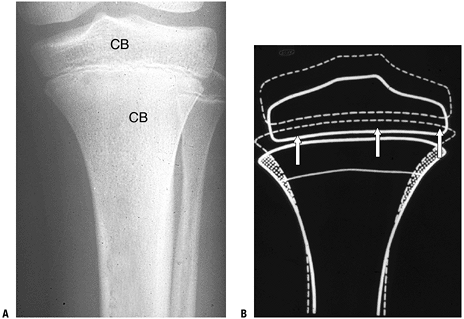

Figure 14-16

Modeling. (A) Cancellous bone (CB) fills the medullary space of the

epiphyses and metaphyses of long bones, transmitting force from the

cortex to the articular surfaces. To maintain the shape of the bone end

as growth occurs, modeling must occur. Modeling is a complex process

with coordinated addition and deletion of bone to achieve an adult

configuration. (B) Diagram shows where bone must be deleted and added

as growth unfolds. At a given time the proximal tibia has the

appearance diagrammed by the solid line. Growth plate action, through

increased cell mass and volume and the secretion of matrix, pushes the

epiphysis away from the metaphysis. The epiphysis grows in width and in

height. The metaphysis widens superiorly and undergoes cutback

inferiorly, narrowing its width to that of the diaphysis. The diaphysis

undergoes lamellar bone apposition to increase its width, while there

is endosteal deletion of bone to maintain cortical width. All deletion

is performed by osteoclasts; addition of bone is by osteoblasts. The

subsequent bone has the contour outline by the dashed line. (Courtesy